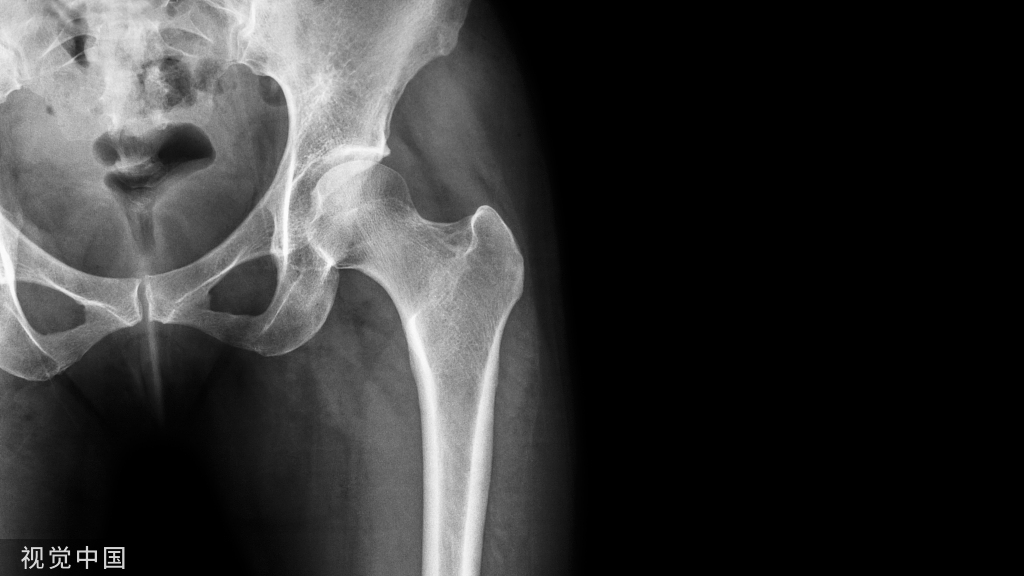

一般而言,会使用X-ray、Bone scan、CT、MRI等影像判别技术协助确诊,而Bone scan(骨扫描)的准确性是当中最高的。

因临床上无典型的外伤史,早期X线平片通常为阴性,容易漏诊或误诊。